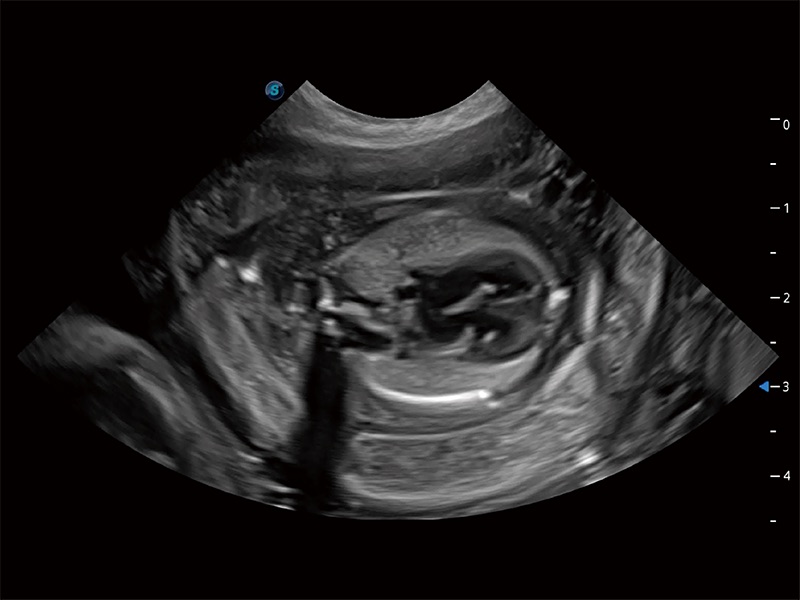

动物是人类最亲密的朋友和最值得信赖的伙伴。乐玩lewin国际也一直致力于探索动物专用的超声影像解决方案。全新推出的ProPet系列,是乐玩lewin国际在动物超声影像智能化、专业化、精准化的一次跨越式革新。动物不能用言语来表述自己的不适,通过超声影像,ProPet系列搭建了动物医生与不同物种沟通的“桥梁”,为动物医生注入了“治愈之力”。 ProPet 80 是乐玩lewin国际匠心打造的一款高端动物专用彩超,采用性能卓越的全新硬件架构,极大提升超声系统的运行效率和数据处理能力,帮助动物医生从容应对日益增多的挑战性病例和日益多样化的临床需求。

高性能和先进的临床应用工具可以为动物医生提供临床信心。ProPet 80 搭载了先进的腹部和浅表应用工具,帮助医生在日常临床实践中发挥前所未有的作用。

ProPet 80 专为动物医生设计,对不同的动物体型和生理结构作出了针对性的优化。通过动物影像专用软件,可满足个性化的应用需求,帮助动物医生获得更精确的诊断数据。